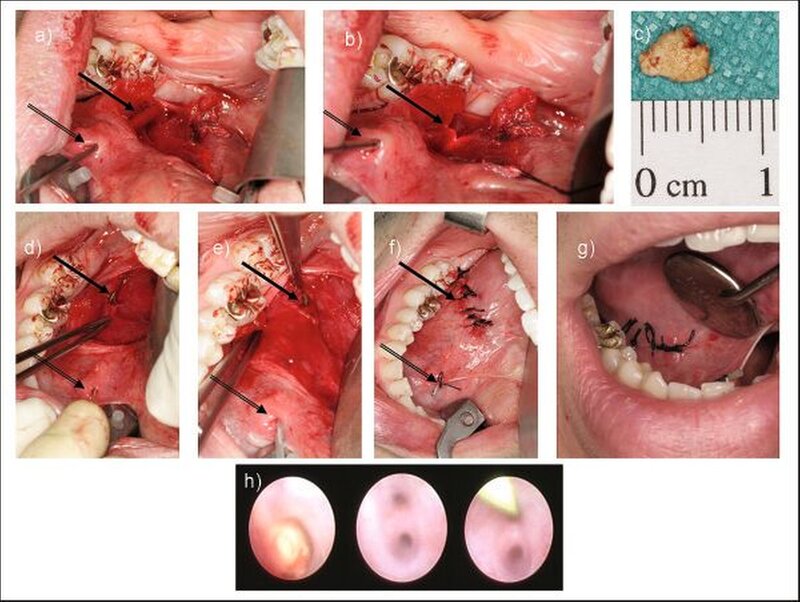

Da Steine von großem Ausmaß (> 8 mm) und langstreckige Stenosen häufig therapierefraktär gegenüber der ESWL beziehungsweise der Dilatation sind, stellen sie eine große therapeutische Herausforderung an die behandelnden Ärzte dar. Das kombiniert endoskopisch/operative Verfahren ist eine Alternative zur operativen Drüsenentfernung und findet sowohl bei der Glandula submandibularis, als auch bei der Glandula parotis Anwendung. Hierbei wird zur Entfernung von großen Steinen die Speichelgangsendoskopie mit der offenen operativen Steinentfernung kombiniert. Bei der Glandula submandibularis erfolgt die Darstellung des Steines durch eine diagnostische Endoskopie. Mittels Diaphansokopie projiziert sich die Steinlage auf den Mundboden und der Operateur kann den Stein lokalisieren. Es erfolgt eine Inzision im Mundboden von etwa 3 cm Länge und die Präparation erfolgt auf das Licht zu. Jetzt kann der Stein gezielt offen chirugisch aus dem über dem Stein inzidierten Gang entneommen werden. Da der N. lingualis den Ductus Wharton von lateral kommend nach medial in den Zungenkörper ziehend unterkreuzt, ist ein besonderes Augenmerk auf die Schonung dieses Nervs zu legen. Nach Entfernung des Steines erfolgt die endoskopische Inspektion des proximalen und distalen Ganganteils, um sicherzustellen, dass keine weiteren Obstruktionen vorhanden sind. Die Einlage eines Führungsdrahtes ermöglicht das Einführen eines Stents in der Seldingertechnik. Abschließend erfolgt der mehrschichtige Wundverschluß im Mundboden (Abbildung 5) [Marchal, 2007]. Vorteil dieses Verfahrens ist, dass auch im Mundboden nicht palpable Steine lokalisiert werden können und im Vergleich zur operativen Drüsenentfernung keine Gefahr der Verletzung des N. facialis und des N. hypoglossus besteht. Zudem entstehen durch den fehlenden extraoralen Zugang keine ästhetischen Beeinträchtigungen. Die transorale Entfernung submandibulärer Steine kann – je nach Steinlage – in Lokalanästhesie oder Vollnarkose durchgeführt werden [Zenk et al., 2001; Capaccio et al., 2005; Chossegros et al., 2006].